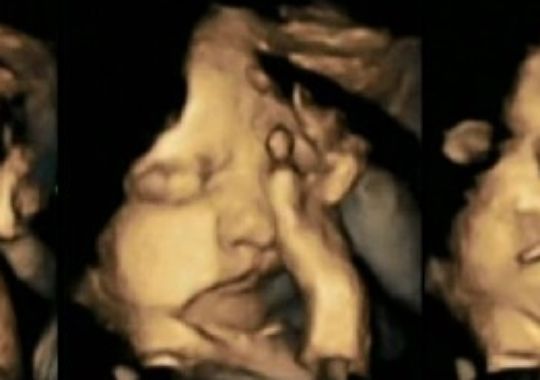

V štúdii, na ktorej pracovala v James Cook University Hospital in Middlesbrough poukázala na to, že nenarodené bábätka sa počas fajčenia dotýkaju tváre omnoho častejšie. Tieto dotyky a tiez zvlastne pohyby úst, alebo doslovne grimasy, boli s postupom vývoja čoraz výraznejšie. Z výsledkov možno predpokladať, že fajčiarky môžu nenarodeným deťom spôsobiť zaostalosť vo vývoji centrálnej nervovej sústavy.